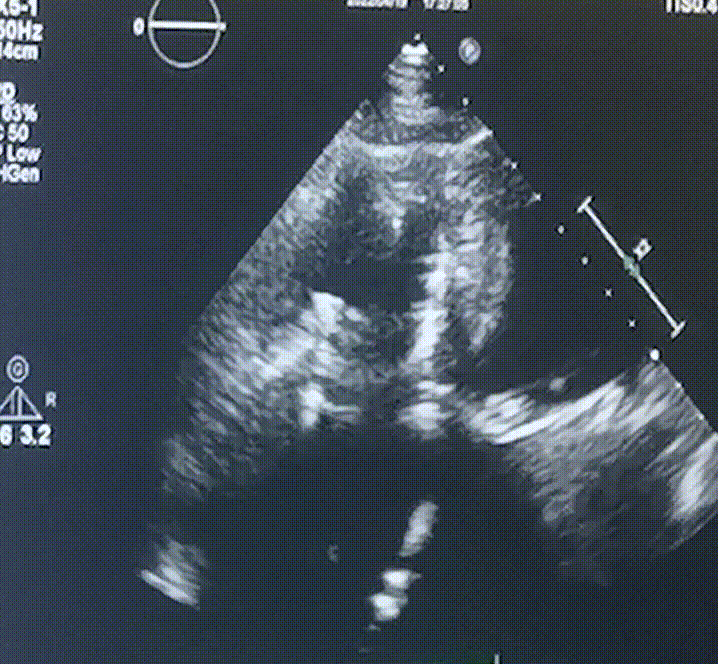

此次手術(shù)在全麻下進(jìn)行,采用經(jīng)右側(cè)頸靜脈入路。術(shù)中在經(jīng)食道超聲和DSA的指引下多個(gè)維度精細(xì)調(diào)整輸送器角度,在達(dá)到正確位置后,逐步釋放瓣膜錨定裝置和盤片,最終完成瓣膜植入。術(shù)后患者右房壓明顯下降,術(shù)后超聲提示人工三尖瓣同軸性良好,瓣架固定牢靠,無反流和瓣周漏,血壓術(shù)后即刻上升20mmHg左右,手術(shù)后監(jiān)護(hù)室順利拔除氣管插管,3天后恢復(fù)良好,予以出院。

圖2.術(shù)后超聲